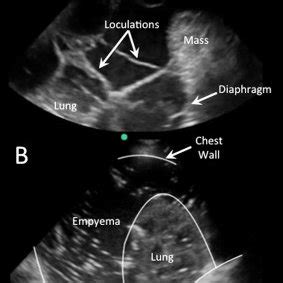

It is commonly known as water on the lungs. If your doctor suspects a malignant pleural effusion, the next step is usually a thoracentesis, a procedure in which a needle is inserted through the chest wall into the pleural space to get a sample of the fluid. The latter are more likely to change with patient positioning 12. Light and rodriguez have proposed a classification and treatment scheme for pleural effusion based on the amount of fluid, gross and biochemical characteristics of fluid, and whether the fluid is loculated. We studied the value of transca … Obliteration of left costophrenic angle with a wide pleural based dome shaped opacity projecting into the lung noted tracking along the cp angle and lateral chest wall suggestive of loculated pleural effusion, however the possibility of empyema can not be ruled out completely. Pleural effusion (basic) large unilateral pleural effusion; Surgical thoracostomy tube placement and radiologically guided catheter drainage are standard therapy for loculated pleural fluid collections.

Loculated effusion) or underlying atelectasis. Blunting of the lateral costophrenic angle usually requires about 175 ml but may take as much as 500 ml. Treatment may fail if the catheter is not placed optimally within the loculation or if the fluid is hemorrhagic or fibrinous. Pleural effusion occurs when too much fluid collects in the pleural space (the space between the two layers of the pleura). May 25, 2021 · the aetiology of the pleural effusion determines other signs and symptoms. Obliteration of left costophrenic angle with a wide pleural based dome shaped opacity projecting into the lung noted tracking along the cp angle and lateral chest wall suggestive of loculated pleural effusion, however the possibility of empyema can not be ruled out completely. The latter are more likely to change with patient positioning 12. Surgical thoracostomy tube placement and radiologically guided catheter drainage are standard therapy for loculated pleural fluid collections.

Strange or atypical configurations of pleural fluid can be due to either adhesions (i.e. Treatment may fail if the catheter is not placed optimally within the loculation or if the fluid is hemorrhagic or fibrinous. Obliteration of left costophrenic angle with a wide pleural based dome shaped opacity projecting into the lung noted tracking along the cp angle and lateral chest wall suggestive of loculated pleural effusion, however the possibility of empyema can not be ruled out completely. Pleural effusion (basic) large unilateral pleural effusion; 18 according to their classification, a transudate is considered as uncomplicated effusion, which can be managed by conservative treatment.